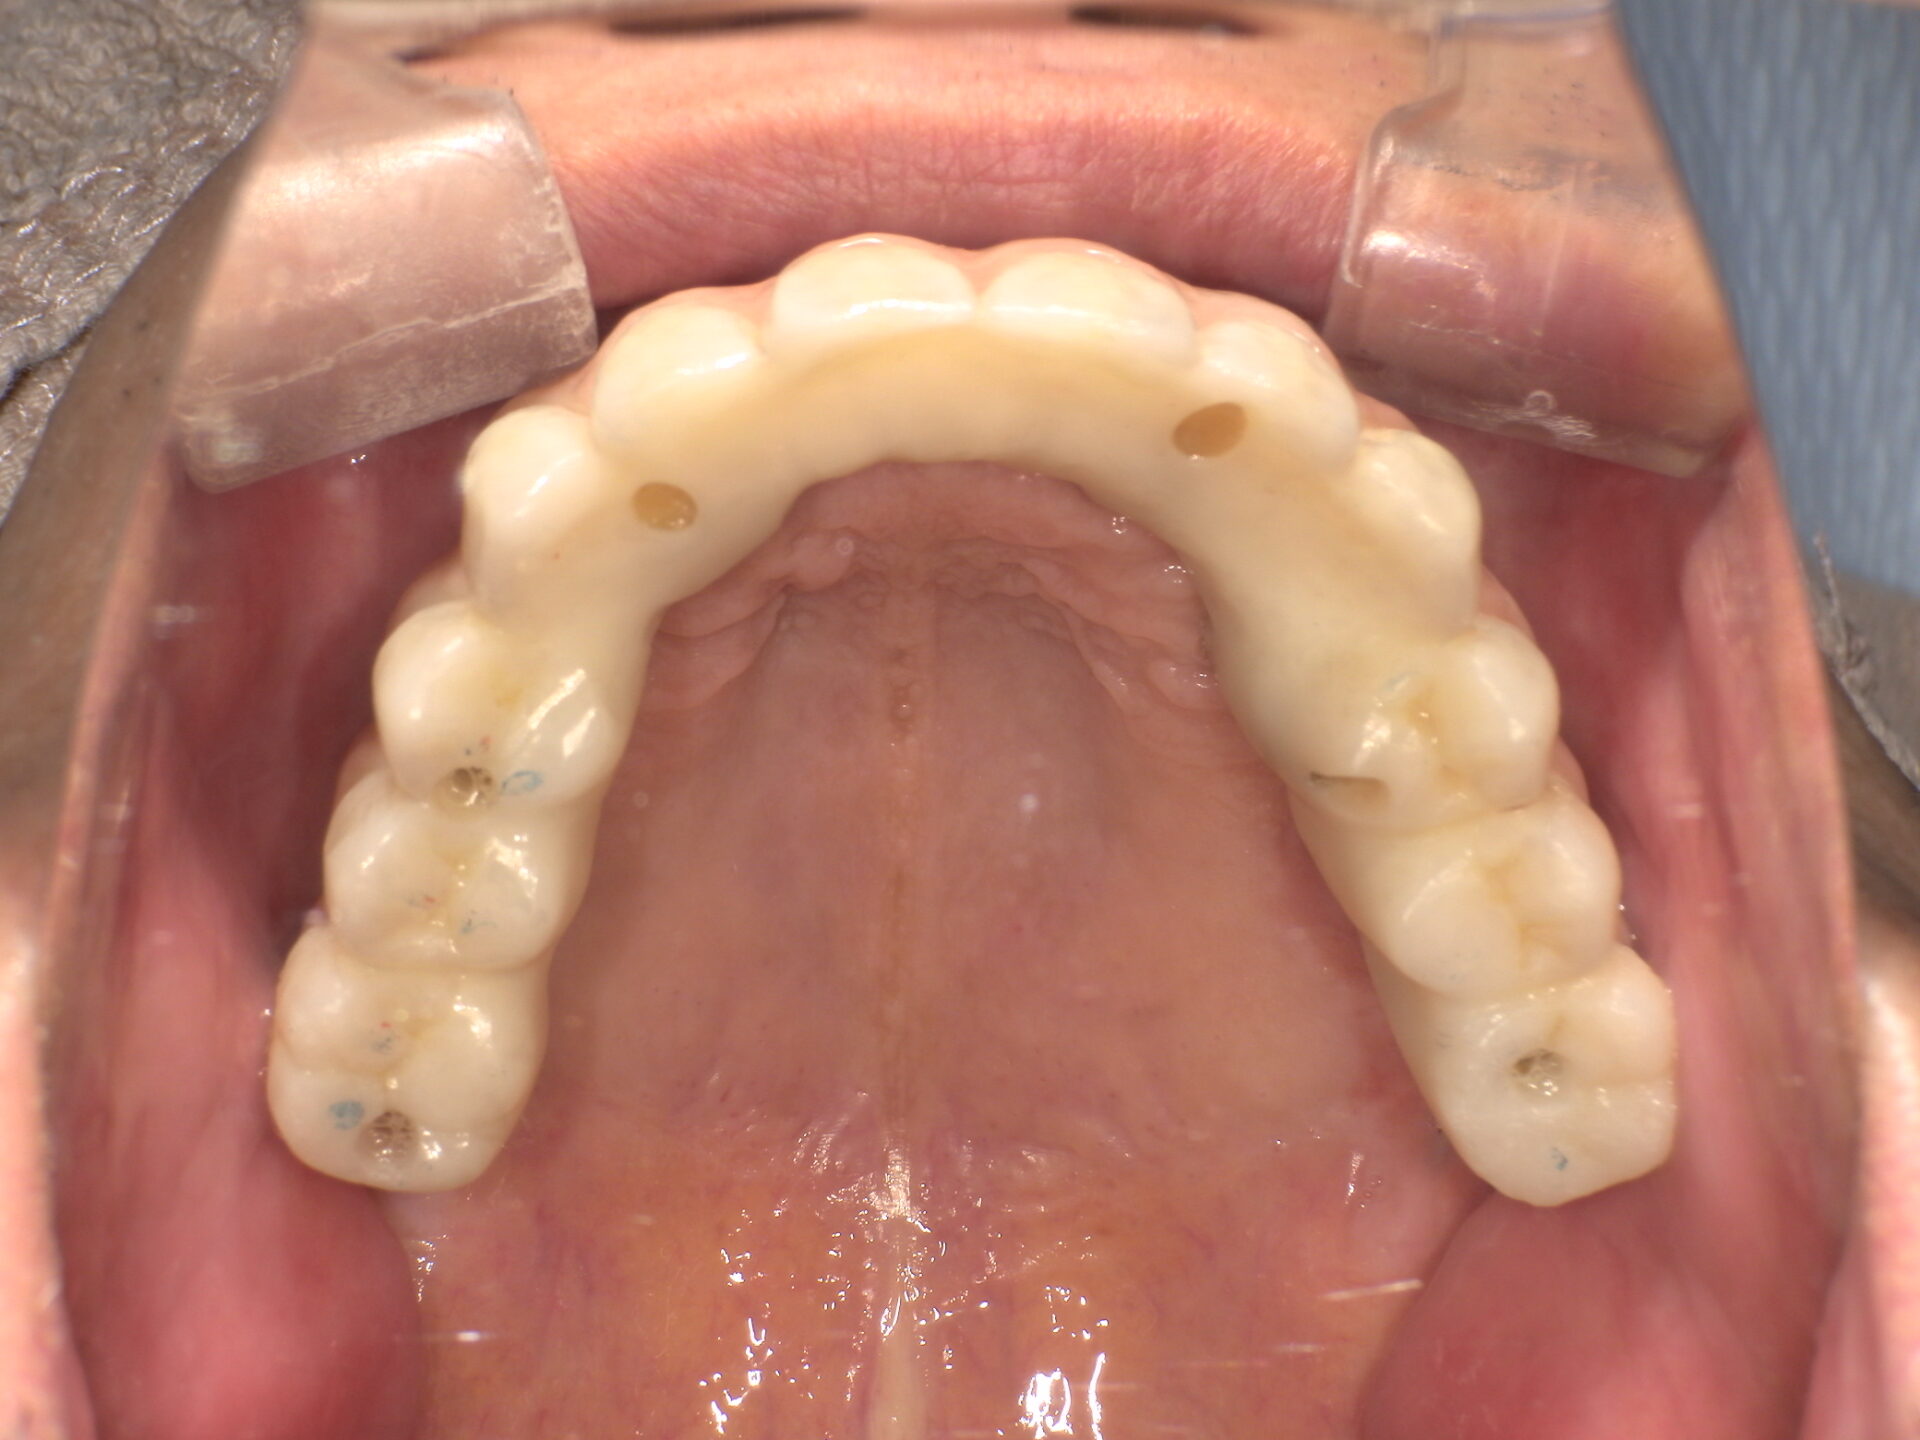

before

after

患者さんの年齢 60代 男性 症状 白い歯を入れて噛めるようにしてほしい 治療内容 インプラント治療(オールオン4) 費用 費用900万(税抜) 治療期間・回数 治療期間2年・通院回数12回 メリット なんでも噛める 見た目が綺麗になった デメリット・リスク 骨造成などで費用が増える場合がある - インプラント治療